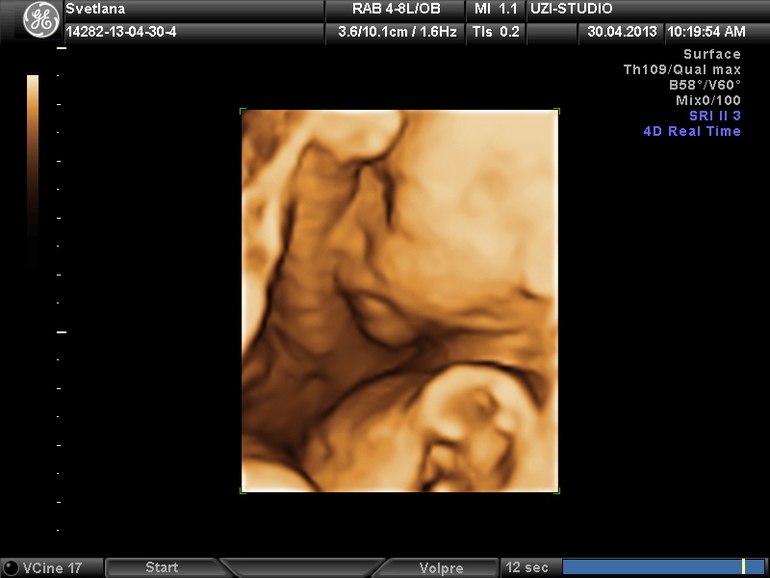

Я со своим ходила, если не ошибаюсь в 31 или 32 недели - раньше не получалось, было все так здорово видно, правда сынок спал и сосал пальчик на ножке) вот фото

по-моему где-то 31-32 недели, помню нам в одной клинике отказали делать 3Д, сказали, что после 29 недель уже ребеночек большой и будет плохо видно, но как оказалось-все было отлично видно и интересно)))